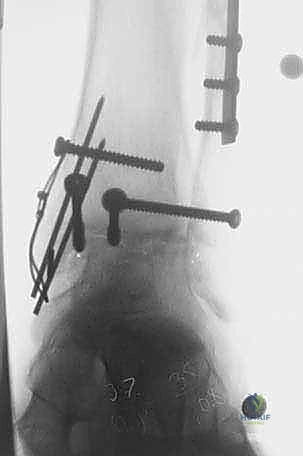

4. زراعة الطعم وتثبيته (Graft Implantation and Fixation)

- يتم تشكيل الطعم المأخوذ من المتبرع ليطابق الحفرة التي تم إعدادها في كاحل المريض تماماً (مثل تركيب قطعة البازل).

- يتم إدخال الطعم برفق (Press-fit).

- لضمان الثبات التام، يتم تثبيت الطعم باستخدام براغي دقيقة جداً (غالباً تكون قابلة للامتصاص البيولوجي أو براغي تيتانيوم غاطسة تحت مستوى الغضروف حتى لا تحتك بالمفصل).

صور إضافية من داخل غرفة العمليات والخطوات الجراحية

ندرك أهمية توثيق الخطوات الجراحية لطلاب الطب والمرضى الراغبين في فهم دقة الإجراء. هذه الصور توضح مراحل زراعة وتثبيت الطعم العظمي الغضروفي بدقة متناهية تحت إشراف أ.د. محمد هطيف.